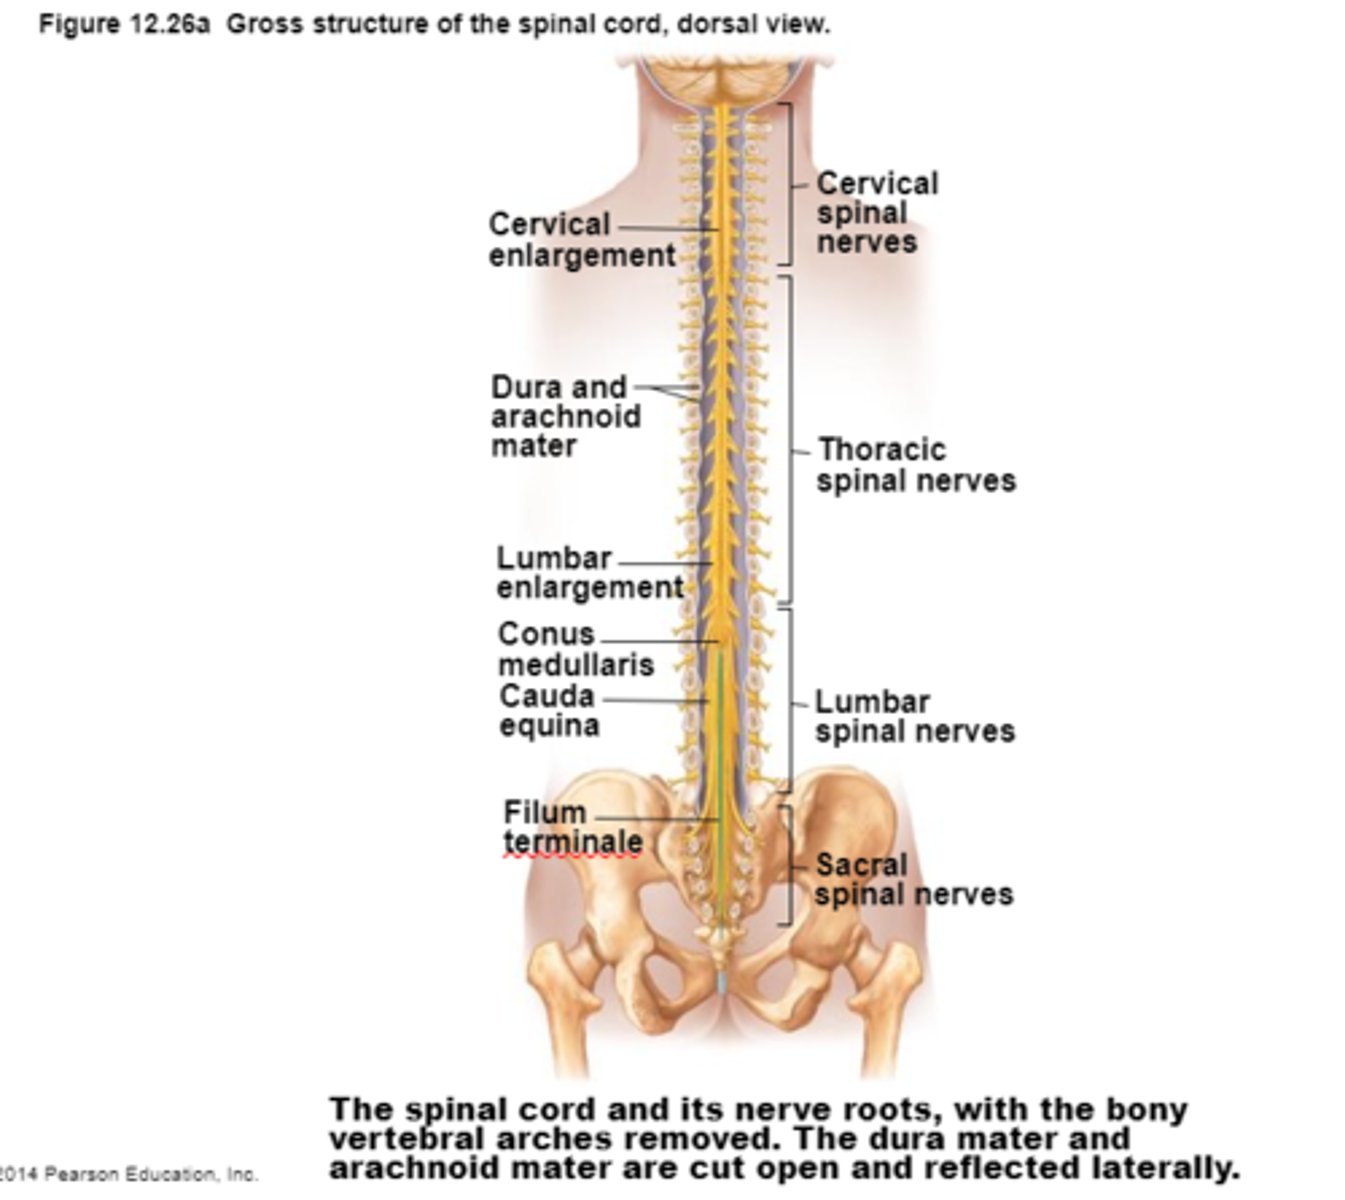

Spinal Cord .

1)Two-way conduction system of nerve pathways to & from the brain

2) Major Reflex center; Spinal reflexes initiated and completed at level of the cord

3) Extends from Medulla Oblongata at level of foramen magnum to the region of L1 or L2

4) Below L2 is the cauda equina

Spinal Cord

Cauda Equina

Bundle of spinal nerves and spinal nerve roots and is below the L2